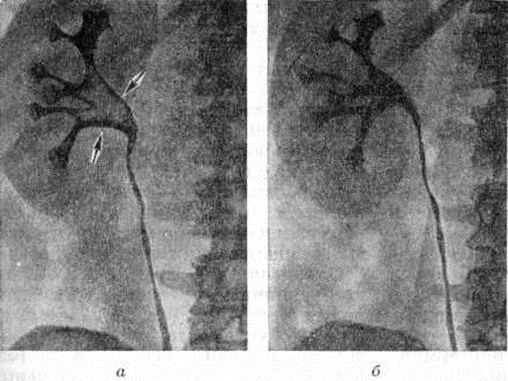

Рис. 7.

Экскреторные урограммы больного почечнокаменной болезнью: а — до лечения; крупный уратный камень, образующий ветвистый дефект наполнения (указан стрелками), чашечки и лоханка расширены; б — после лечения: контрастное вещество равномерно заполняет весь объем чашечек и мочеточника, дефект наполнения лоханки отсутствует.

Больным с уратными (рентгенонегативными) камнями при удовлетворительной функции почек и уродинамике, отсутствии острого пиелонефрита назначают так называемый растворители — препараты цитратов (магурлит, солуран и другие). Дозировка их индивидуальна и регулируется в процессе лечения в зависимости от pH мочи (необходимо поддерживать pH в пределах 6,2—6,9). Курс лечения 1½—2½ месяцев с последующим контрольным рентгенологическое исследованием. В ряде случаев лечение даёт положительный результат (рисунок 7). При отсутствии эффекта повторные курсы лечения нецелесообразны.